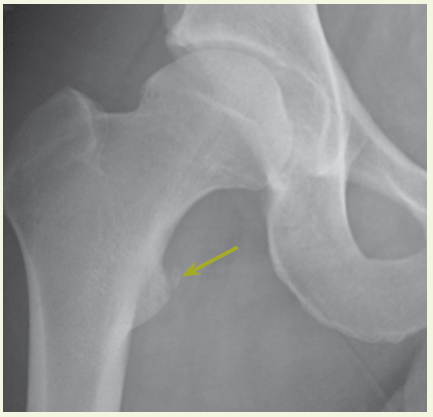

A radiograph of the pelvis showed avulsion of the lesser trochanter.

Discussion. In avulsion fractures of the pelvis, the involved muscle may be identified by the location of the fracture and, when the patient can tolerate a muscular strength evaluation, certain resistance testing clues:

• Pain with hip flexion and rotation: iliopsoas muscle has pulled off part of the lesser trochanter, as in this patient.

Avulsion fractures of the pelvis are most common in patients between the age of 11 and 15 years. The differential diagnosis includes muscle strain and periostitis. Consider osteomyelitis or tumor in patients with groin pain who have asymmetric radiographic findings and no history of trauma.